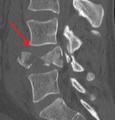

A burst fracture of L4 as seen on CT